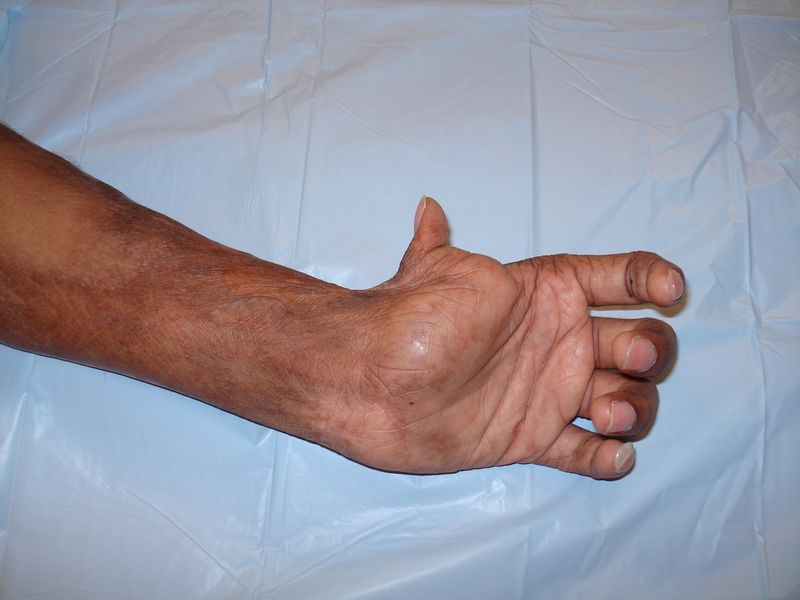

3. Namaste Program (Reconstructive Hand Surgery):

Getting both hands to work to serve the society. This encompasses the surgeries for the correction of acrodactyly, syndactyly, macrodactyly, club hand, claw hand, burn contracture release to name a few.